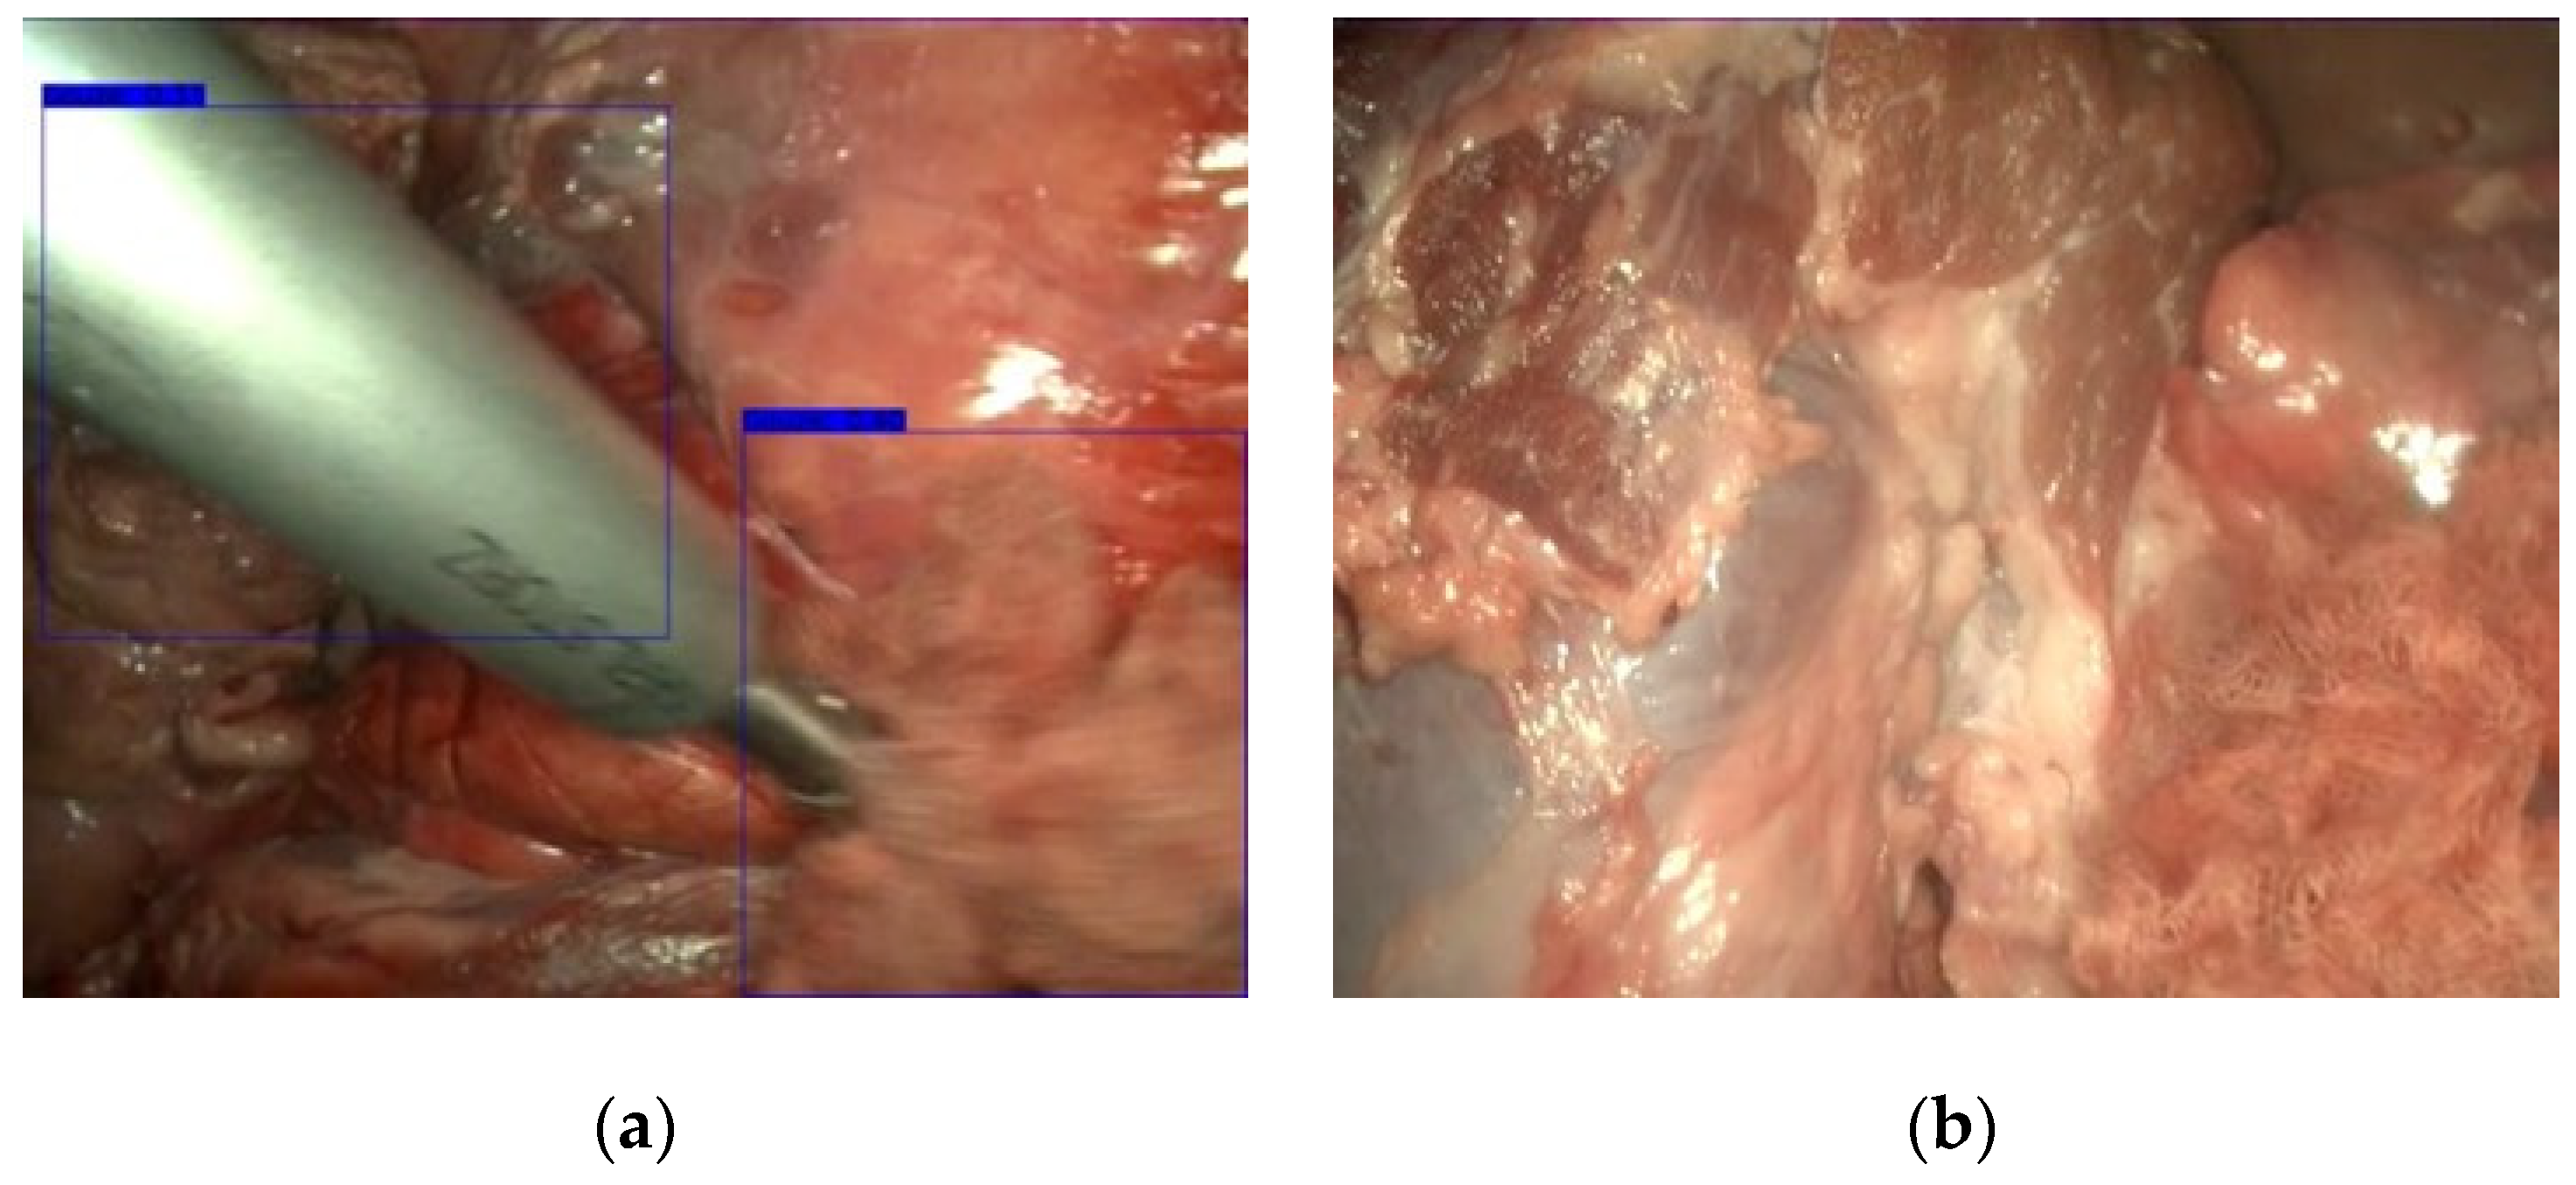

3.2. Gauze Coarse Segmentation